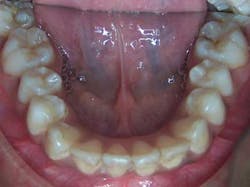

From the beginning, Rachael’s dad wasn’t convinced that his daughter needed orthodontic treatment. After all, her teeth were already relatively straight, as can be seen in the photos below.

Rachael’s dad was reluctant to even schedule a consult appointment, but his dentist insisted that significant improvements could be made to Rachael’s appearance. The fact is that both Rachael’s dad and the dentist were correct in their assessments. In other words, the teeth won’t look much straighter, but Rachael’s appearance would be significantly improved. How could that be?